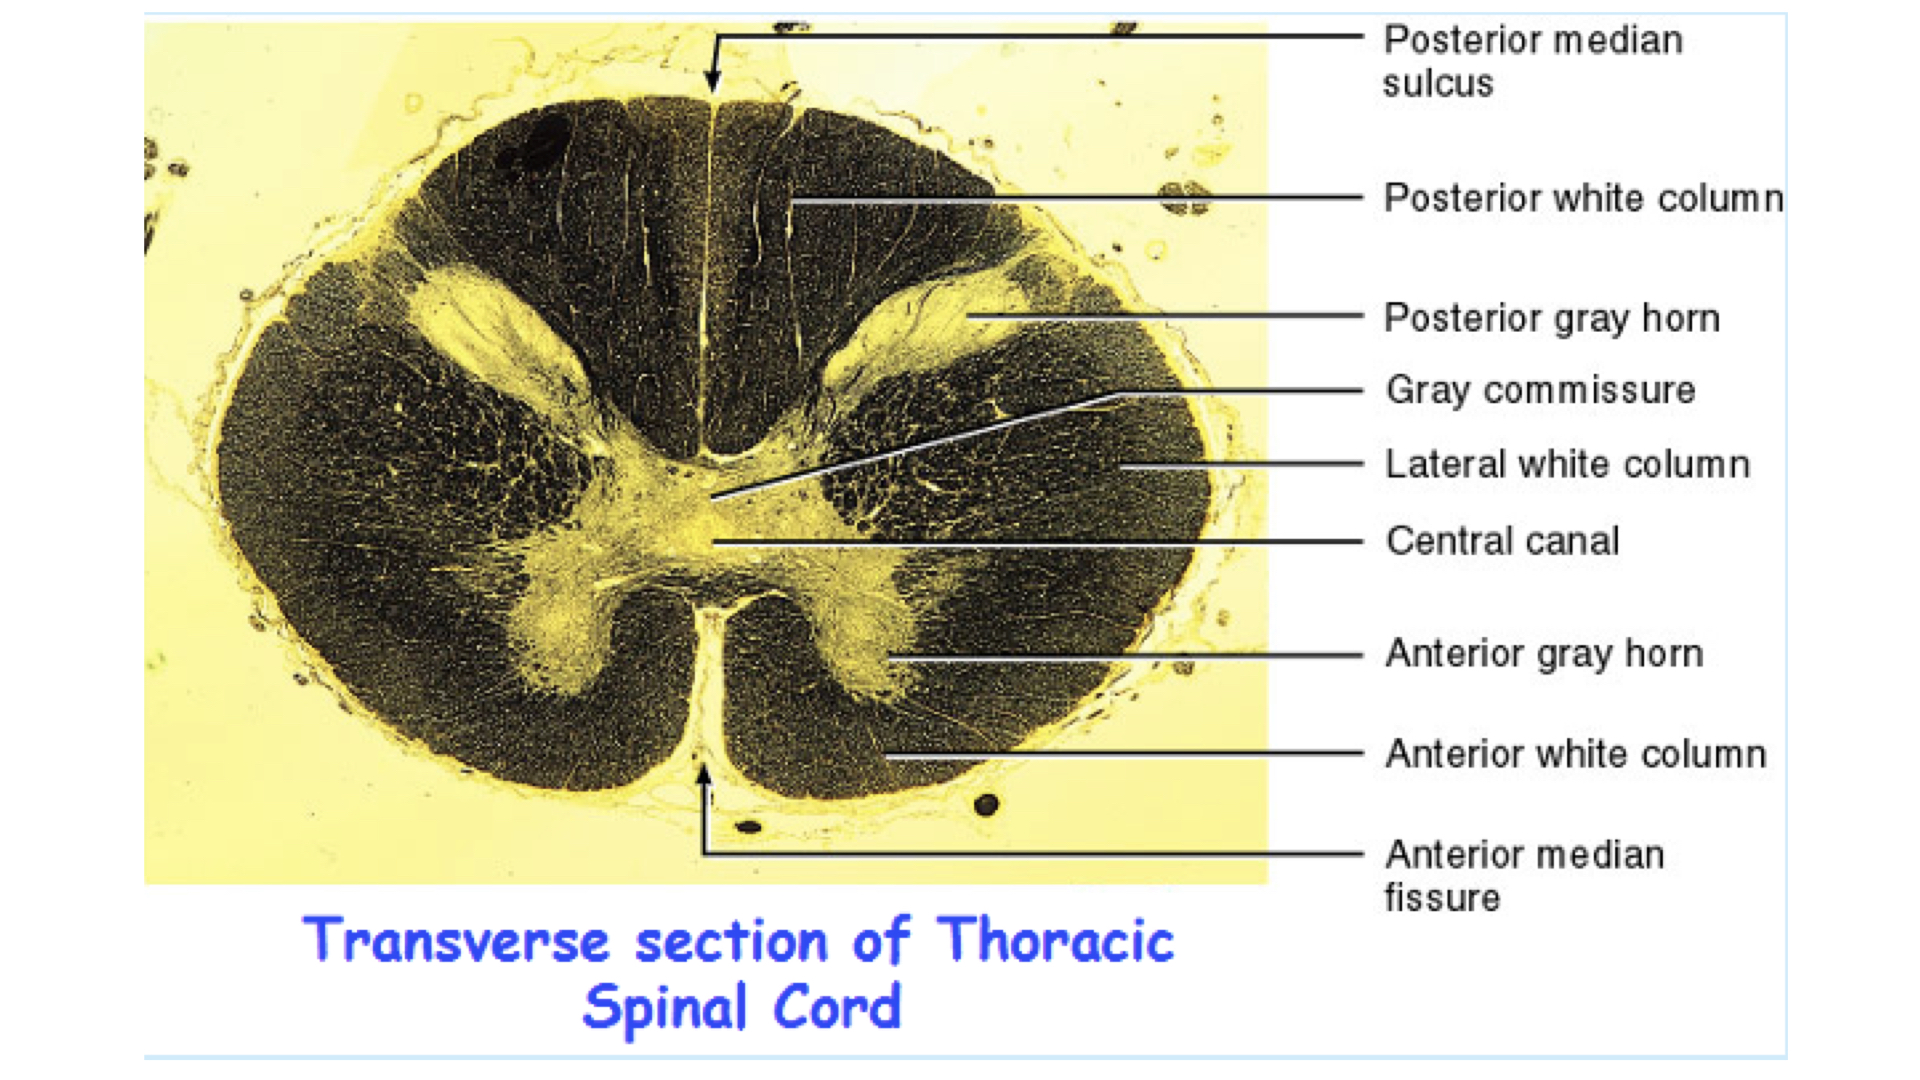

4. Composed of gray & white matter – histologically H shaped grey matter surrounded by white matter

a. Gray matter - unmyelinated tissue, mainly cell bodies, soma, nissl bodies

b. White matter - myelinated tissue, mainly axons

4. Anterior median fissure – deep groove along the ventral surface

5. posterior median sulcus – shallow groove on the dorsal surface

1. Gray matter

a. Composed of neuron cell bodies,shaped like an H or butterfly

b. Six projections called horns:

1. Two dorsal gray horns

2. Two ventral gray horns

3. Two lateral gray horns - found in thoracic lumbar

c. Transverse bar called the gray commissure

d. Central canal in center of gray commissures

2. White matter

1. Anterior median fissure

2. Posterior median sulcus